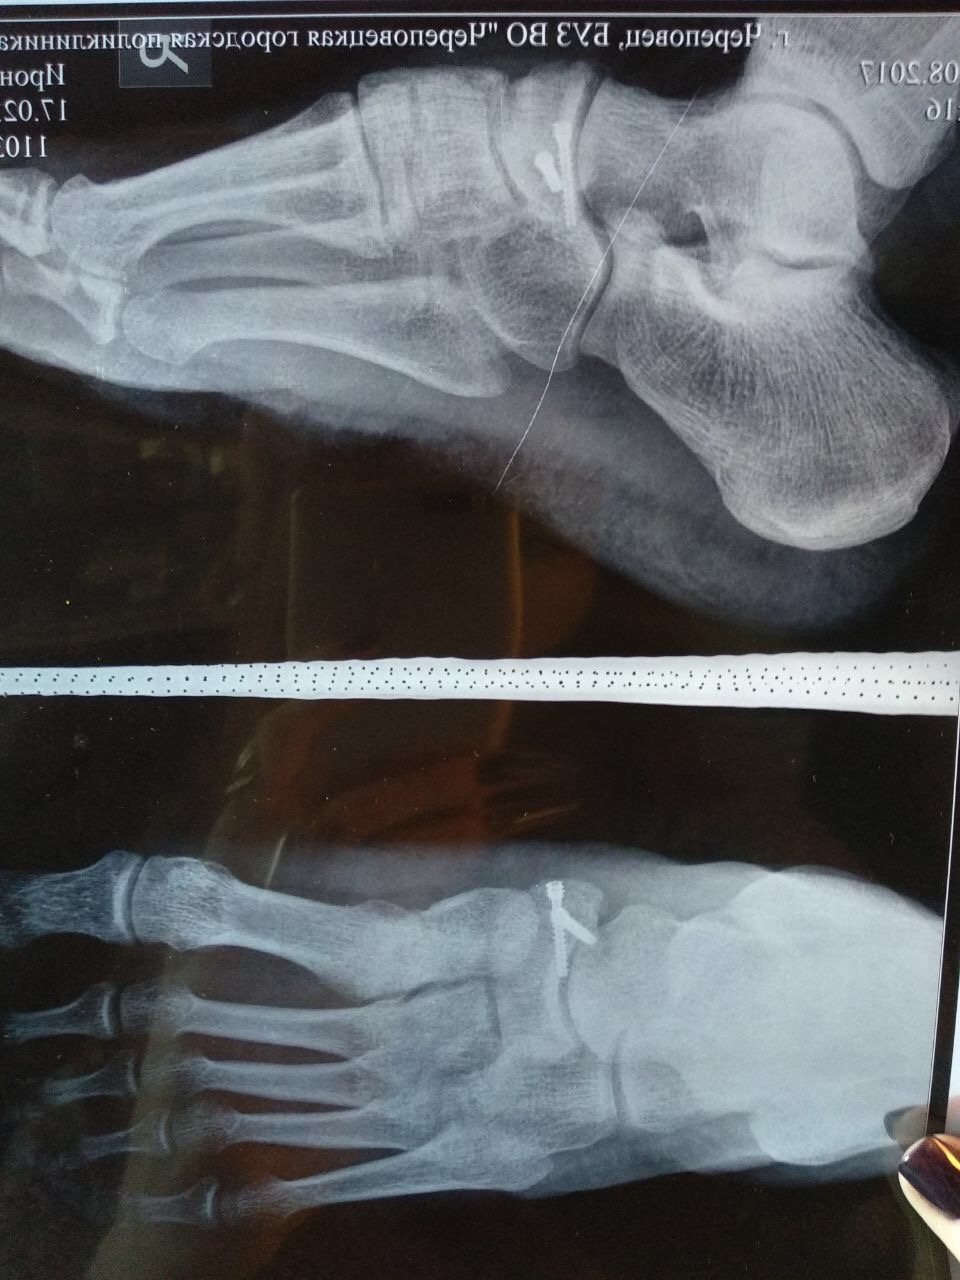

Блог Как "СanadaPeptides" ногу залечила=]

Тема в разделе "Персональные блоги", создана пользователем Kabran, 30 июн 2017.